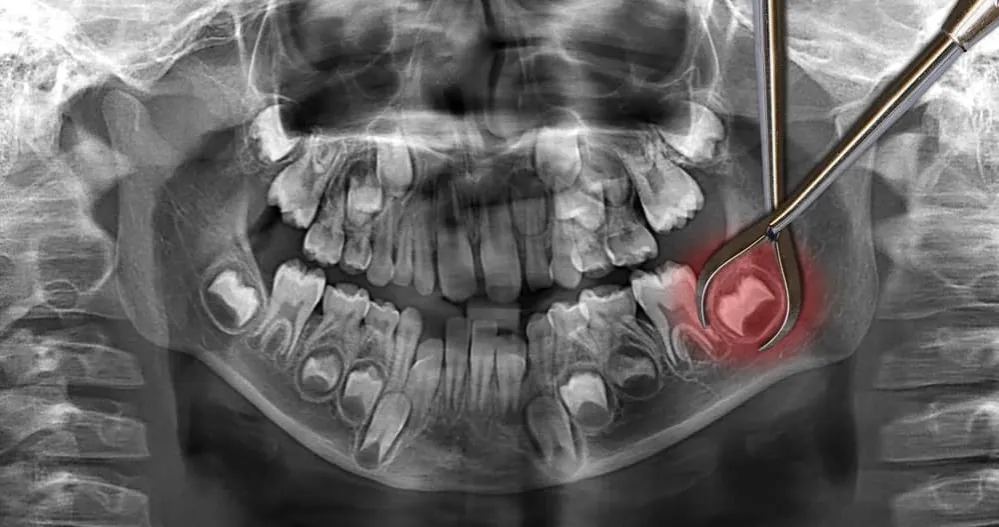

Ząb zatrzymany w kości: analiza kosztów najbardziej skomplikowanego zabiegu

Najbardziej złożonym i co za tym idzie, najdroższym zabiegiem ekstrakcji jest usunięcie zęba całkowicie zatrzymanego w kości, najczęściej dotyczy to właśnie ósemek. Taki ząb nie wyrzyna się prawidłowo i pozostaje ukryty pod dziąsłem lub w kości szczęki. Jego usunięcie wymaga zaawansowanych technik chirurgicznych, a cena takiej procedury może sięgnąć od 800 zł do nawet 1200 zł. Jest to zabieg często wykonywany przez chirurga szczękowego, co dodatkowo podnosi jego koszt.